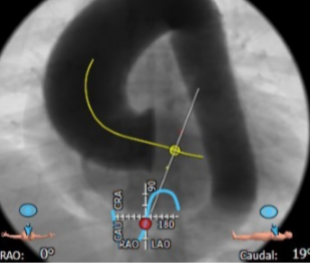

瓣环平面测量

定位两个窦底

瓣环平面周长82.5mm,直径26.3mm

(二叶瓣/极重度钙化)

体位选择

选取合适的投射角度,两个窦底部在平面上,同时无冠窦在最低点

可以术中造影确认角度是否合适

横位心 接近90°